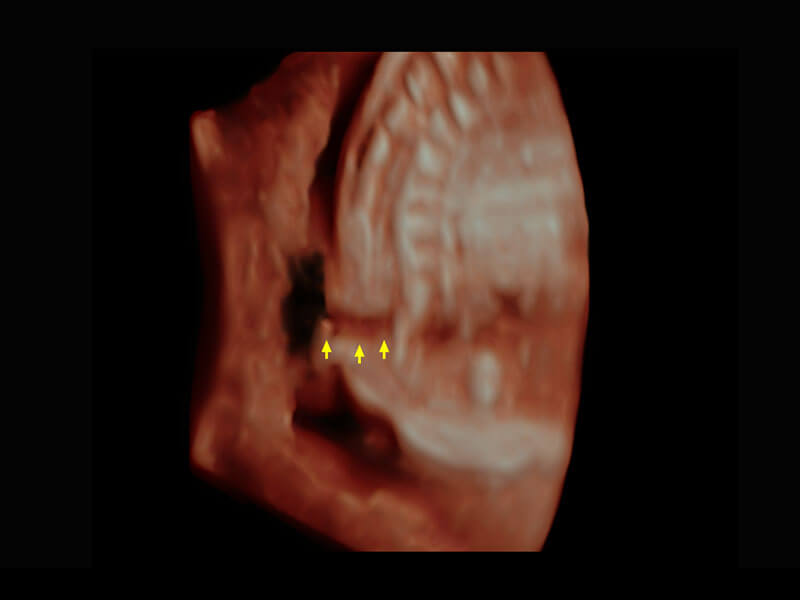

P60搭载一系列胎儿心脏成像技术,实现精细的胎儿心脏评估。

右室双出口